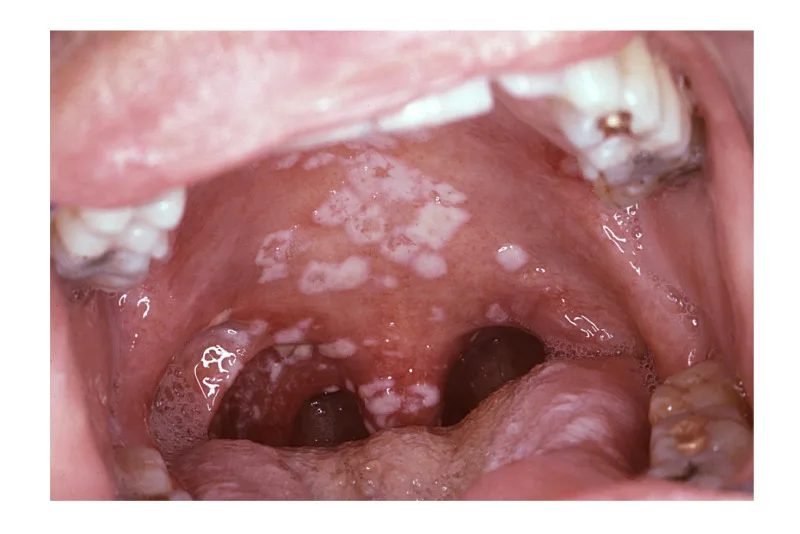

- بقع بيضاء: أحد الأعراض المميزة لمرض القلاع الفموي هو وجود بقع بيضاء أو كريمية أو تشبه اللبن الرائب على اللسان أو داخل الخدين أو سقف الفم أو اللثة أو الحلق. يمكن كشط هذه البقع بسهولة، لتكشف عن أنسجة حمراء وفي بعض الأحيان تنزف تحتها.

السلاق الفموي البيضاء

السلاق الفموي البيضاء أو المبيضات البيضاء هذا هو النوع الأكثر شيوعًا من الفطريات المرتبطة بمرض القلاع الفموي. تظهر على شكل بقع أو لويحات بيضاء على اللسان، والخدود الداخلية، وسقف الفم (الحنك)، والجزء الخلفي من الحلق.

قد يكون للبقع مظهر يشبه الجبن ويمكن كشطها بسهولة، مما يترك سطحًا أحمر اللون وينزف أحيانًا. يمكن أن تؤثر المبيضات البيضاء على كل من الرضع والبالغين، وخاصة أولئك الذين يعانون من ضعف في جهاز المناعة، أو الأفراد الذين يتناولون أدوية معينة (مثل المضادات الحيوية أو الكورتيكوستيرويدات)، أو أولئك الذين يعانون من حالات صحية كامنة.